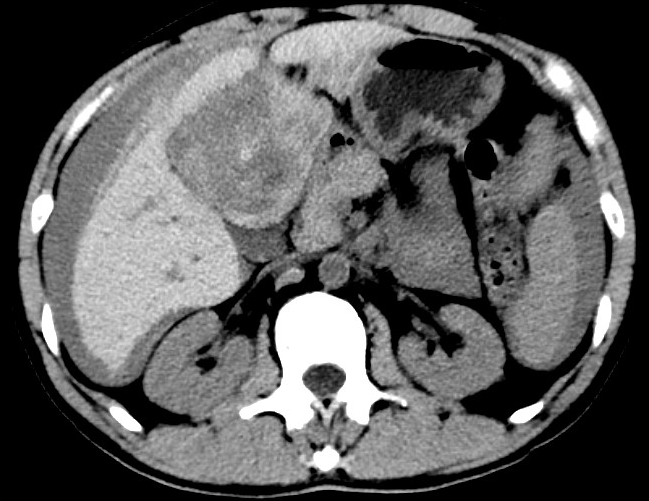

放下電話的白葦急赴消內(nèi)三搶救室會診,經(jīng)仔細查體、對患者腹部CT進行詳細閱片、綜合評估患者后,考慮患者是肝占位破裂出血?;颊卟∏槭志o急、一刻也不容耽誤,需立刻急診行肝動脈造影 栓塞術(shù)進行止血治療,在與患者家屬溝通后,立即通知消化介入室準備急診手術(shù)。

入手術(shù)室時,患者神志迷糊,口唇干燥、重度貧血貌,心電監(jiān)護提示:心率140-160次/分,血壓70/43mmHg,這是失血性休克的表現(xiàn)!白葦快速建立靜脈通道緊急給予輸血,升壓,止血等液,立即給予肝動脈造影,術(shù)中發(fā)現(xiàn)肝左葉疑似腫瘤病灶、病灶周圍血管分支有造影劑外溢,考慮血管破裂出血,迅速給予栓塞微球進行肝動脈栓塞。整個手術(shù)過程不足20分鐘,術(shù)后即刻患者心率降至100-110次/分、血壓升至90/60mmHg。

術(shù)后給予積極抗炎,止血,保肝、利尿等對癥治療,復(fù)查血常規(guī)提示活動性出血停止后,在超聲引導(dǎo)下行腹腔穿刺引流術(shù),術(shù)后3天共引流出血性腹水約4000ml。患者經(jīng)復(fù)查各項指標均趨于正常,復(fù)查CT提示腹腔積血已基本吸收,患者康復(fù)出院。